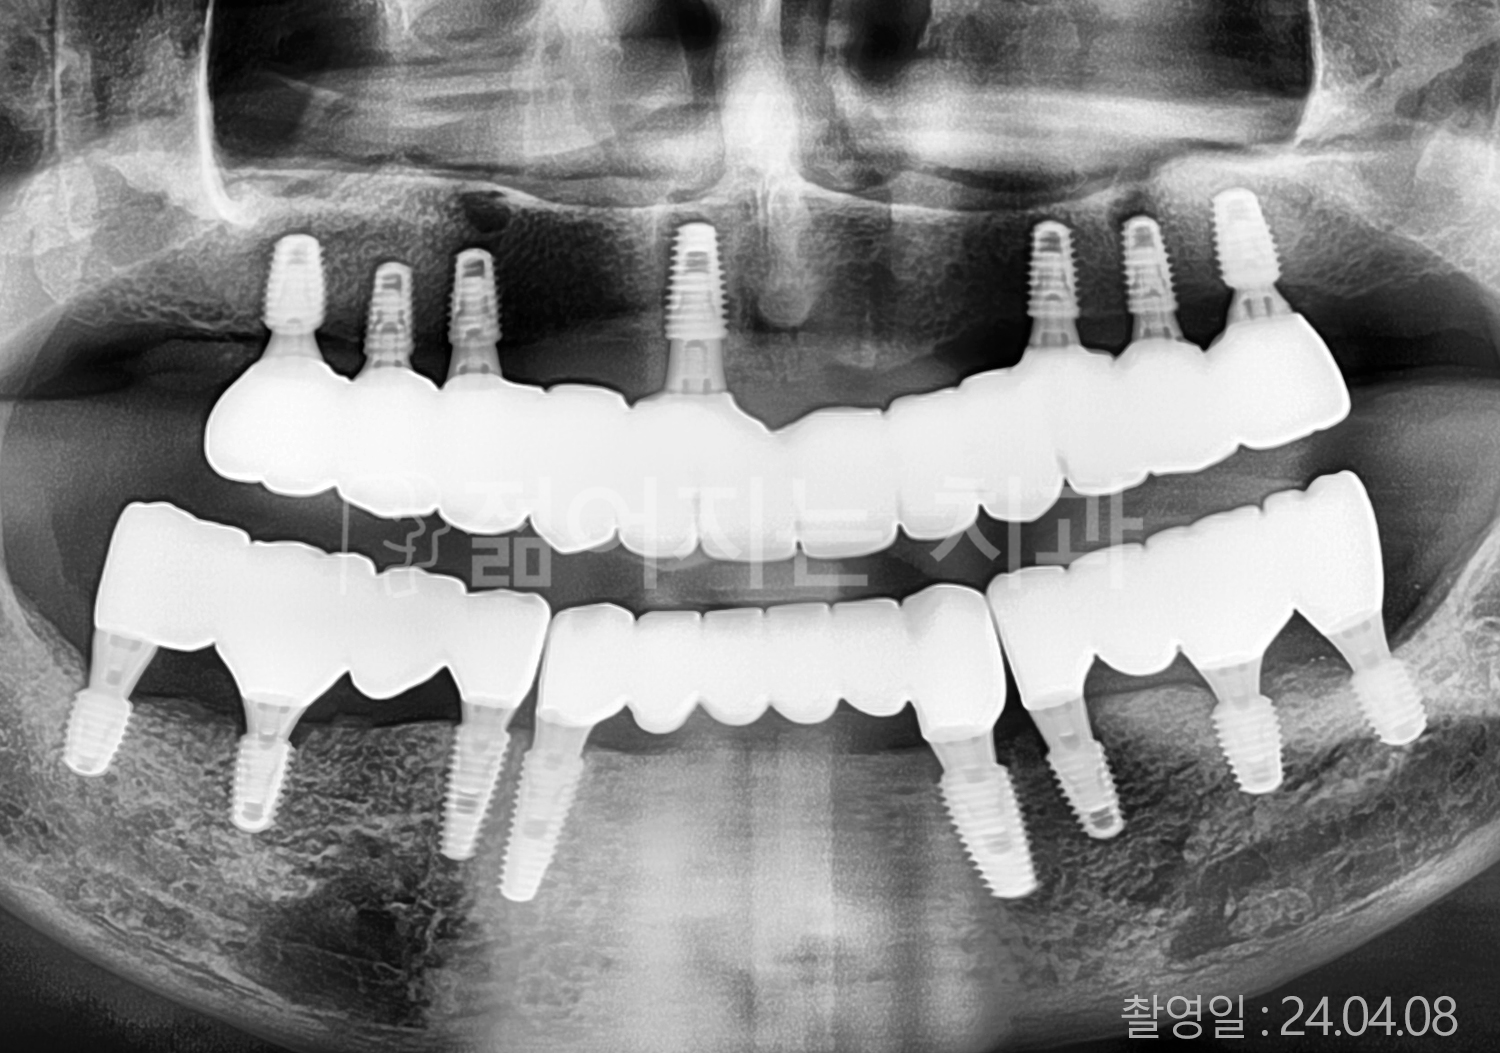

• 70대 고혈압, 당뇨 전체치아 10개 이상 임플란트

• 50대 고혈압, 당뇨 전체치아 10개 이상 임플란트

• 60대 고혈압, 당뇨 전체치아 10개 이상 임플란트

• 50대 전체치아 10개 이상 임플란트

• 70대 당뇨 전체치아 10개 이상 임플란트

• 80대 전체치아 10개 이상 임플란트

• 40대 전체치아 10개 이상 임플란트

• 60대 고협압, 고지혈증 전체치아 10개 이상 임플란트

• 60대 전체치아 10개 이상 임플란트